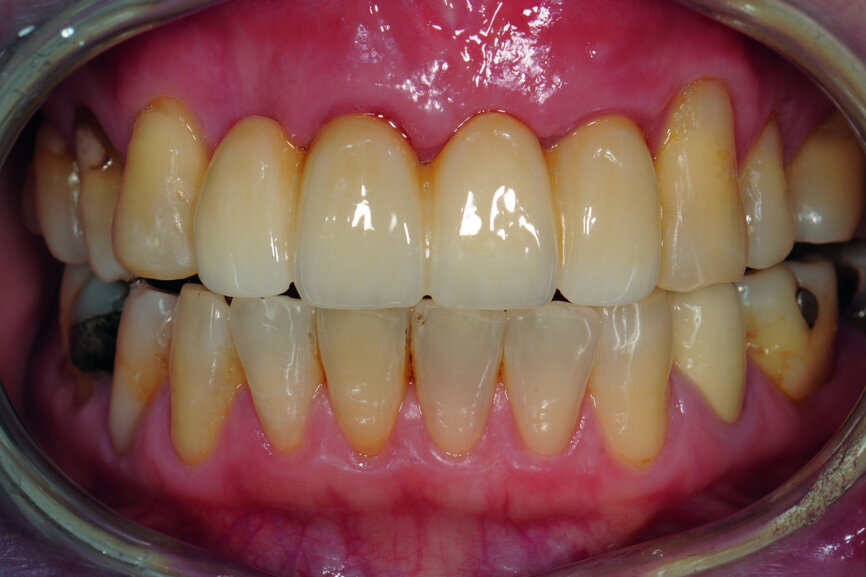

A 40-year-old female patient had sustained trauma to her anterior teeth caused by accidental syncope three weeks before. The clinical examination found that tooth #11 had been luxated; the crowns of teeth #12 and 21 had fractured, with the residual margin extending 3–5 mm below the gingiva and the teeth affected by Grade III mobility; and the crown of tooth #22 had fractured, with the residual margin at gingival level. There were no obvious abnormalities in the remaining teeth (Figs. 1–4). After excluding major systemic diseases, it was decided that she required fixed implant restoration with high demands regarding aesthetics and function.

Fig. 48: Frontal view of the anterior teeth after two weeks.

The cast model was scanned step by step to obtain a digital model and this was integrated with a virtual articulator. The anterior guidance of the virtual articulator was set according to the data from the provisional restoration. Next, the design was completed on computer and the titanium-based zirconia abutment and fixed zirconia bridge produced via CAM. After staining and glazing, the final restoration was completed (Figs. 34–41). The final restoration demonstrated a good outcome, both aesthetically and functionally (Figs. 42–50).